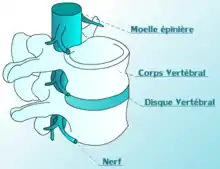

Un disque intervertébral (DIV) ou fibrocartilage intervertébral est un cartilage qualifié de fibreux, qui se trouve entre presque toutes les vertèbres de la colonne vertébrale (sauf entre C1/C2). Chaque disque est formé d'un fibro-cartilage mixte (se rapprochant d'une symphyse), et permet un faible mouvement des vertèbres. Il agit aussi comme un ligament maintenant les vertèbres ensemble. Son rôle d'amortisseur des chocs est crucial et son altération physiologique explique les nombreuses pathologies du dos.

Les disques intervertébraux sont constitués d'un anneau fibreux externe, l'annulus fibrosus, qui entoure une substance gélatineuse interne, le nucleus pulposus[1].

Schéma vertèbre et disque intervertébrale

Schéma vertèbre et disque intervertébrale Image d'une cage d'arthrodèse par voie d'abord antérieure, il existe également des prothèses (ou disque artificiel) permettant de conserver la mobilité